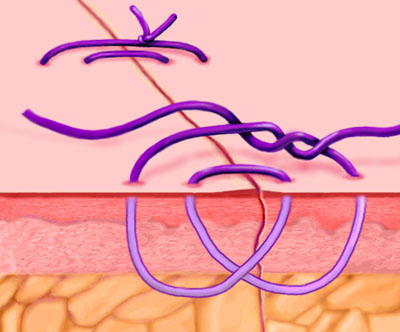

Smead-Jones/Far-and-Near

A double loop technique alternating far and near stitches, and possessing greater mechanical strength than continuous or simple interrupted sutures. Commonly used for approximating fascial edges, especially for patients at risk for fascial disruption or infection

Continuous Locking, or Blanket Stitch

A self-locking running stitch used primarily for approximating skin edges